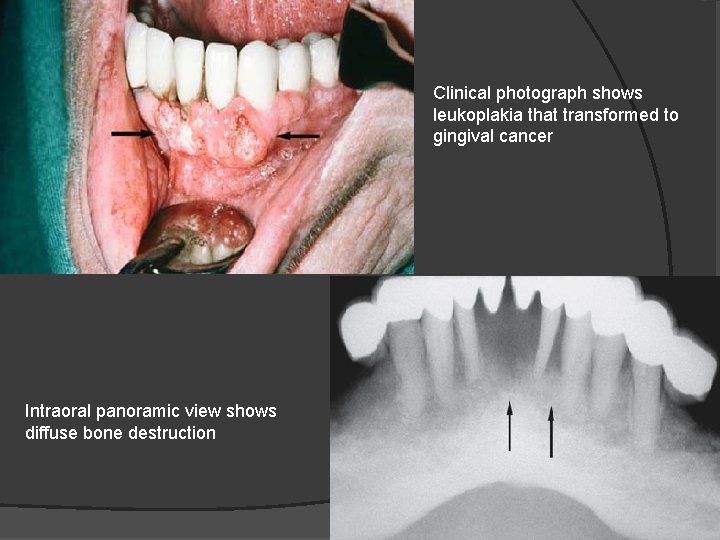

Clinical photograph shows leukoplakia that transformed to gingival cancer Intraoral panoramic view shows diffuse bone destruction